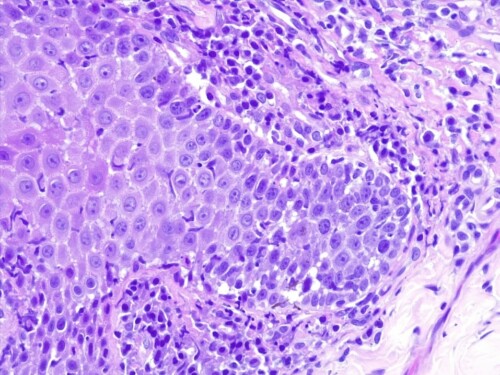

L’examen histologique des coupes de lésions croûteuses colorées à l’hématoxyline et à l’éosine révèle une hyperplasie parakératosique, avec de petites vésiculo-pustules intra-épidermiques contenant des éosinophiles et quelques cellules épithéliales acantholysées, un infiltrat lichénoïde avec des lymphocytes, des plasmocytes, des macrophages, des cellules dendritiques et des mélanophages dans les machons péri-annexiels. Aucun élément bactérien ou parasitaire n’est observé.

Figure 4: Agrandissement plus important. Un infiltrat lichénoïde (Figure 3) formé de lymphocytes, de plasmocytes, de macrophages, de cellules dendritiques et de mélanophages (H&E x400).

Cet aspect histologique a révélé une dermatite micro-pustuleuse granulocytaire intra-épidermique acantholytique et amicrobienne et des lésions de dermatite d’interface lymphocytaire. Cette association lésionnelle de dermatite lichénoïde d’interface et de dermatite pustuleuse acantholytique est caractéristique en dermatologie vétérinaire d’une forme rare de pemphigus superficiel présentant les caractéristiques du lupus érythémateux cutané chronique : le pemphigus érythémateux.